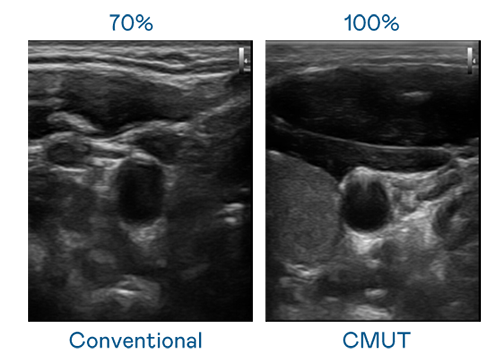

CMUT 技术是一种用电容式微机电元件来产生超音波讯号的技术。与传统 PZT 压电式技术相比,CMUT 频宽增加 30%,更宽频的超音波讯号让影像解析度大幅提升,是实现高影像品质医疗超音波扫描、促进精准医疗发展的关键技术。

超音波影像的解析度高低,首先取决于探头能发出的讯号频宽。菠菜导航 CMUT 可提供高清晰的超音波讯号,提供高频宽、高灵敏度、影像纹理细节更高的超音波影像,协助医护人员缩短影像判读时间及利用精准的医疗影像进行诊断。